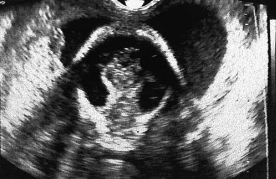

The sonographic finding in this image is most suspicious for:

ventriculomegaly